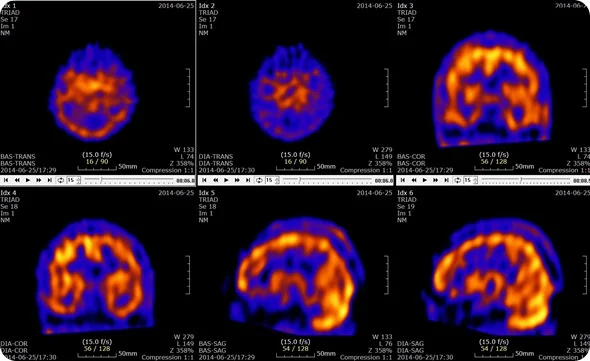

9) PET ( Positron Emission Tomography)

આ એક ઇમેજિંગ સ્ટડીઝ છે કે જેમાં રેડિયોએક્ટિવ મટીરીયલ્સ નો યુઝ કરી બ્રેઇન tissues માં injury તથા ડેમેજ થયું હોય તો તેને ડિટેક્ટ કરવા માટે યુઝ થાય છે.

PET એ મુખ્યત્વે Parkinsonism, Tumors, Alziemers તથા Seizure હોય તો તેને અસેસ કરવા માટે યુઝ થાય છે.